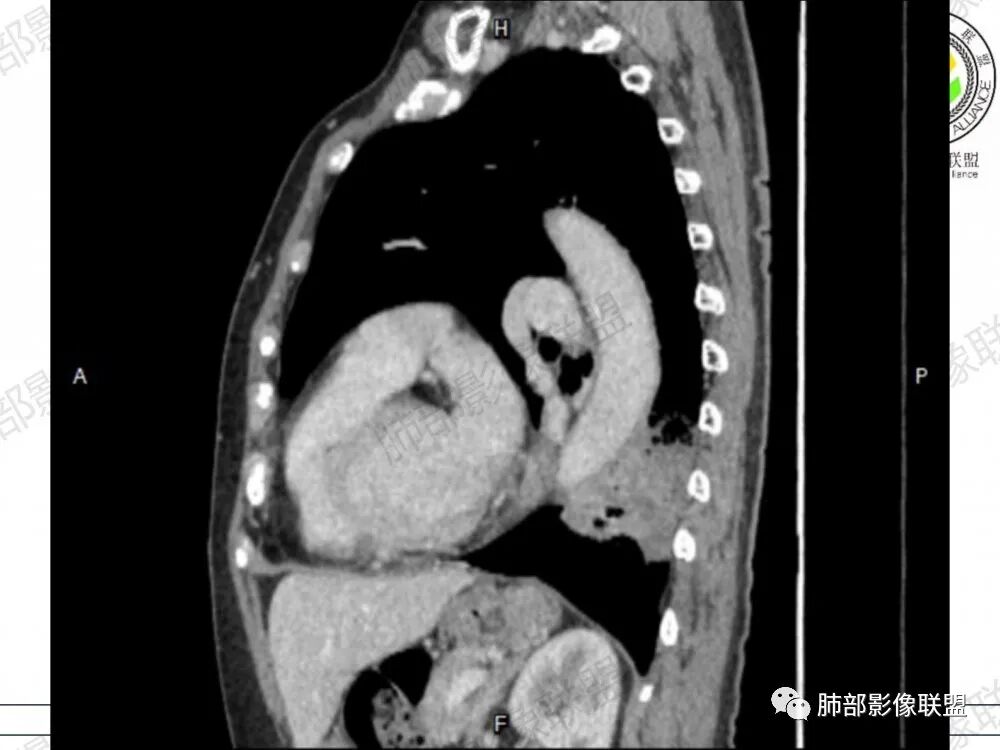

2、影像表现:无肺气肿背景,病变定位于左肺下叶背内侧基底段,病灶呈不规则团块影,靠近胸膜侧,其内密度不均匀,内见空洞、实变及磨玻璃影,磨玻璃影呈碎石路征,边界清楚,实性肿块边界膨隆,其内见空洞。空洞周围比较实。病灶较大的支气管通畅,细小的支气管成“枯枝征”。无胸膜增厚及胸膜腔积液,增强扫描呈中度强化,见血管造影征。

1、粘液型腺癌仅占肺原发腺癌的3%左右,粘液多,易气道播散,支气管破坏不明显,不仅是大的支气管,小的支气管大多也没破坏,较大的支气管通畅,细小的支气管充满粘液,从而形成“枯枝征”,本病例病灶内可见枯枝征,是诊断粘液腺癌特点之一。

2、典型的粘液腺癌,收缩力很弱,肺泡壁断裂常有,张力存在,早期较少出现张力表现,破坏力偏弱,支气管与肺血管大多保留,所以增强病灶内见强化血管影(血池),也是粘液腺癌另一个特点。

3、 由于粘液重力作用,粘液腺癌易发生于下肺胸膜下,由于小叶间隔阻挡,胸膜侵犯少,通常是胸膜与周围肺组织的模糊增厚,粘液腺癌的胸膜侧较宽,但胸水少见也是诊断特点之一。